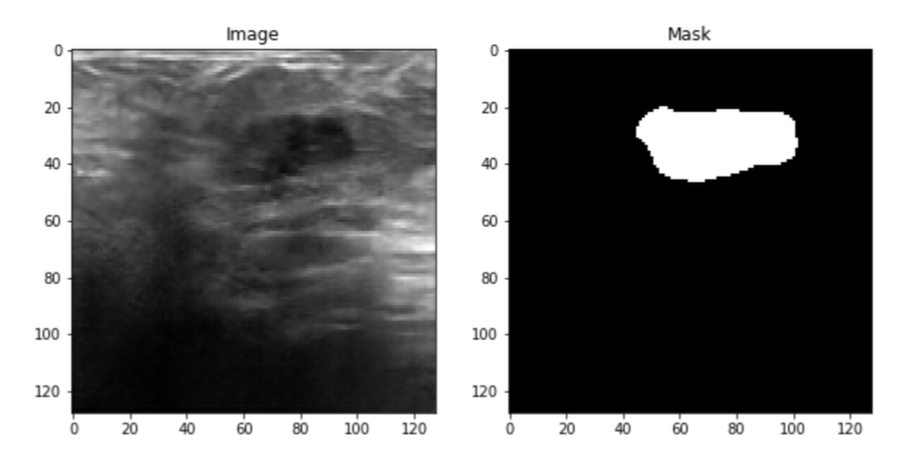

Four datasets were used, the first one is the Baheya dataset which includes a total of 780 ultrasound images. These images are split into three categories Benign, Malignant, and normal, and each category includes 437, 210, and 133 respectively. Also, each ultrasound image has its mask images as shown in the figure below.

The second dataset is Bus-synthetic-dataset, which consists of 500 breast ultrasound images, and each image has its mask same as the first dataset as shown in the figure below.